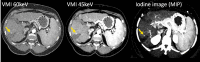

Novel photon-counting detector CT (PCD-CT) has the potential to address the limitations of previous CT systems, such as insufficient spatial resolution, limited accuracy in detecting small low-contrast structures, or missing routine availability of spectral information. In this review article, we explain the basic principles and potential clinical benefits of PCD-CT, with a focus on recent literature that has grown rapidly since the commercial introduction of a clinically approved PCD-CT.